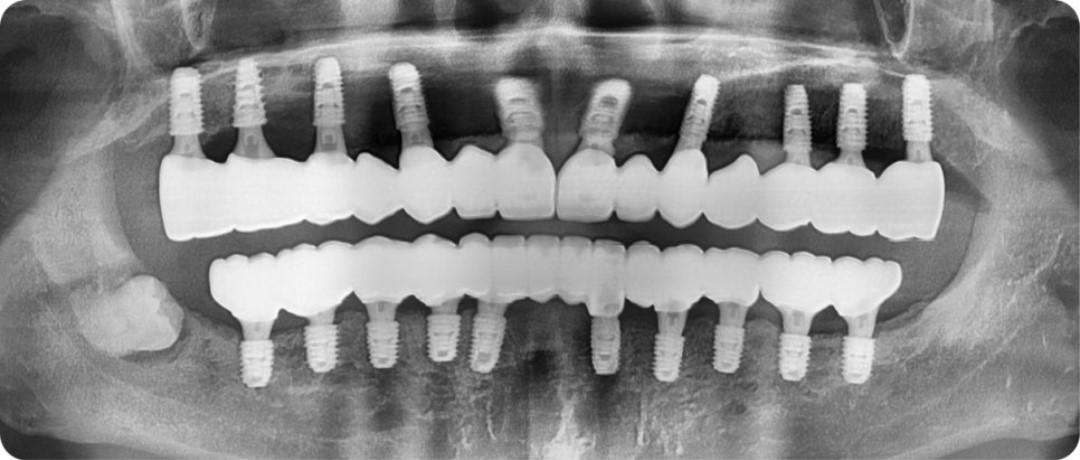

e92146487e92c.jpg

강한 저작력을 충분히 견딜 수 있을 정도로

튼튼한 기초공사를 해드렸기 때문에

담배 안 피우고, 구강 위생관리만 철저하게 잘 해주신다면

충분히 튼튼하게 오래 사용하실 수 있으실 겁니다.

94af261d36a7a.jpg

구강 사진을 봐도 보철물이 상당히 자연스럽고

교합 또한 안정적으로 잘 설계된 모습입니다.